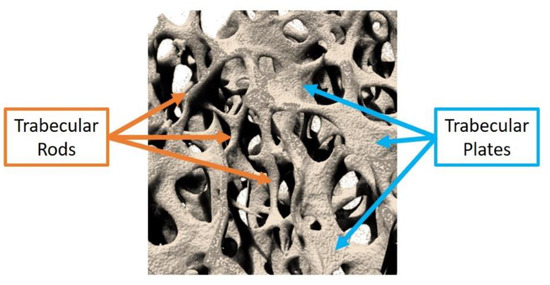

Trabecular bone is composed of numerous plate-like and rod-like trabeculae that arrange themselves according to the applied mechanical stress; their relative proportion depends on the bone site (Figure 3). In general, plates align along the longitudinal axis of bone and sustain most of the load, while rods are disposed along the transverse plane and act as links to stabilise the structure [29].

Figure 3.

Rod and plate distribution in a human humeral head (3D rendering executed by the authors by scanning the bone sample with a micro-computed tomographer at a resolution of 3 µm).

Chen and Kubo [22] observed an increase in the rod-like proportion with ageing and OP due to the conversion of plate-like trabeculae into rod-like ones in several human bone sites (vertebra, femur and distal radius). Gentzsch and collaborators [30] tried to explain this conversion mechanism by monitoring the resorption lacunae present on the trabecular compartment of various femoral heads of cadavers, concluding that the centre of trabecular plates is a preferential site for the formation of resorption lacunae. In the presence of a continuous erosion process not counterbalanced by an effective bone matrix refilling by Ob, the resorption cavities deepen and develop into plate perforations, leading to the final conversion of plates into rods. Since resorption lacunae and plate perforations represent discontinuities in the bone structure, they are preferential regions of microfracture triggering, leading to an overall reduction of bone resistance to the applied loads.

A common indicator used in bone research studies to determine the balance between rods and plates is the structure model index (SMI), exploiting the measurement of the bone surface curvature. Ideally, the SMI value is zero for a plate and three for a cylinder, therefore, the variation of bone SMI between these extremities can indicate the prevalence of one trabecular structure over another. Considering that in the osteoporotic bone a conversion of trabecular plates in rods is normally observed, superior values of SMI are usually reported compared to those registered for the healthy tissue [31].